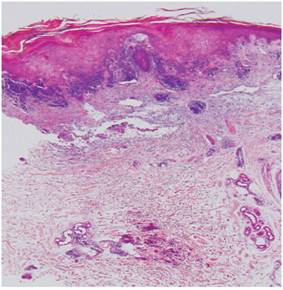

Biopsia de piel y músculo (Figuras 4 y 5): infiltrado perivascular de linfocitos en el plexo profundo, inflamación a predominio linfocítico de vasos del perimisio y atrofia perifascicular.

Existen otros síntomas y signos que pueden presentarse, como neumonitis intersticial, afectación cardíaca y disfagia, como se observó en esta paciente. Las alteraciones enzimáticas propias de la DM plantean diagnósticos diferenciales como enfermedades malignas, hepatopatías e infarto del miocardio. La DM en asociación con procesos malignos constituye un síndrome paraneoplásico. Algunos autores 5 señalan la incidencia entre un 13 %-15 % y otros 6 entre el 20 %-30 %. Los datos ofrecidos por la biopsia de piel y músculo muestran una inflamación perimisial y perivascular, y puede ocurrir atrofia perifascicular, lo que ofrece el diagnóstico.